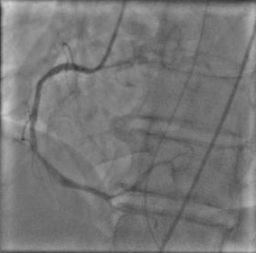

X-ray angiography is the most used imaging modality to visualise blood vessels for interventional purposes such as stenting of stenosed vessels or for diagnostic purposes such as assessment of myocardial perfusion or stenosis grading. To minimise ionising radiation exposure of the patient and medical personnel during image acquisition, low power X-Rays are used resulting in noisy and low contrast images. In the context of diagnosis, the main object of interest is the vascular tree, its branchings and variations in thickness. It is therefore necessary to accurately highlight the vessels in consecutive frames to reduce the noise and improve contrast. In addition, in interventional procedures, identifying interventional instruments (catheter, wires) is also needed in order to better plan and control their positioning. Efficiently discriminating between instruments and vessels as well as other anatomical structures that may have similar appearance is crucial during the interventions. Figure 1(a-c) shows an example of an angiogram sequence. Note large non-rigid motion between frames as well as the ambiguity between vessels and the catheter. Figure 1(e) shows a frame from a different sequence of the same patient but taken at different scan and angle and (f) shows a different patient. There is a significant difference in vessel as well as catheter locations in all three sequences, which we consider as independent examples. Figure 1(d) shows the ground truth segmentation of the first frame.

The dataset consists of anonymised fluoroscopy X-Rays of 26 different patients. The images were acquired during stent placement using a General Electric Innova 2000 system and stored according to standard medical protocol in DICOM format. In total the dataset includes 36000 frames corresponding to 365 distinct video sequences with an average of 98 frames each. Different sequences of the same patient were taken at different angles and stages of the procedure therefore they differ significantly as shown in Figure 1(c)(e)(f). Each frame is rescaled from to due to memory constraints.